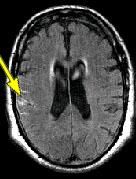

IMAGING FINDINGS: The CT was performed on AIC’s new 16-slice helical multi-slice CT (MSCT). Both routine single-slice and thin-section helical scans were obtained and 3D/Multiplanar images were performed on the Advanced 3D workstation. Fig. 1 shows an image at the level of the lateral ventricles with possible high density within the sulci on the right (arrow). To confirm this finding, an MRI with contrast was then obtained on AIC’s 1.5-Tesla high-field, short-bore Siemens MRI. Fig. 2a-b are T2-weighted images at the same level showing NO definite abnormality. T1-weighted images (not shown) were also negative. The post-contrast images (not shown) showed NO abnormal enhancement in this region, either. Diffusion-weighted images were also negative. However, Fig. 3a-b, which are FLAIR images, demonstrate clear hyperintensity within multiple sulci involving the right temporo-parietal area (arrows).

DIAGNOSIS: The FLAIR images are compatible with Subarachnoid disease. The Differential Diagnosis includes: (1) Subarachnoid Hemorrhage (SAH); (2) Meningitis; (3) Infarct; (4) Flow Artifact. Lack of enhancement is against meningitis. Acute infarct was ruled out on the basis of negative Diffusion MRI and lack of cytotoxic edema on the FLAIR images. Focal abnormality is against flow artifact (which is more diffuse and usually in the posterior fossa on FLAIR images). The clinical history of trauma and the high-density on CT and hyperintensity on FLAIR images within the sulci are diagnostic of Acute Post-traumatic Subarachnoid Hemorrhage (SAH).